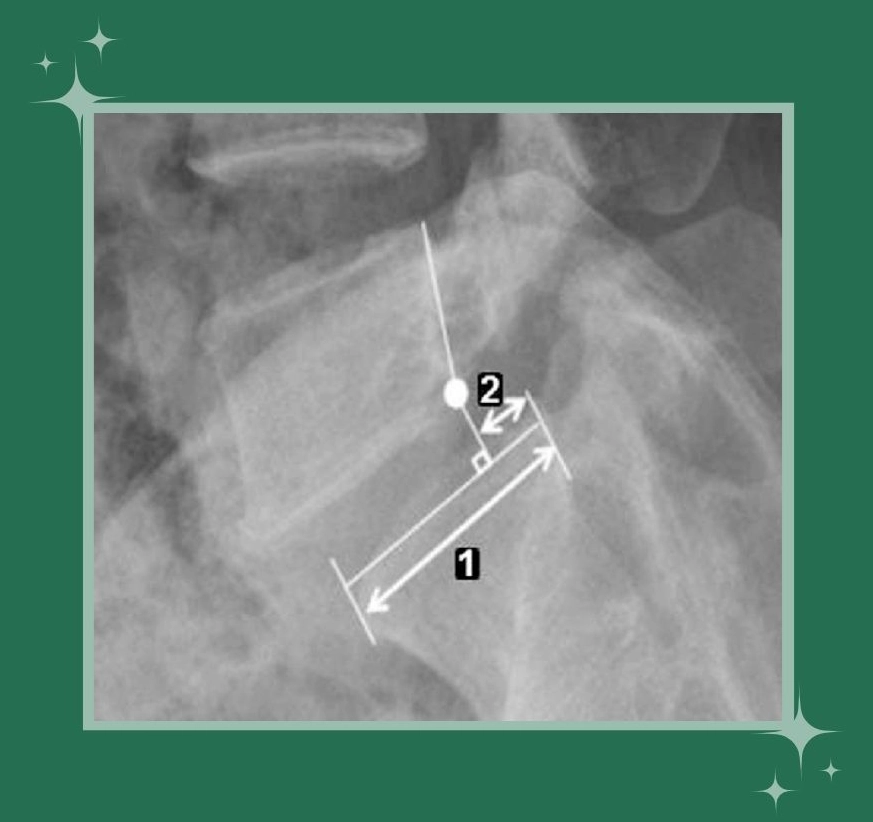

رادیوگرافی ساده (X-Ray): بهترین روش اولیه برای تشخیص است و میزان سرخوردگی مهره را نشان میدهد. تصاویر از زوایای مختلف (ایستاده، خم و باز شدن) میتواند بیثباتی را مشخص کند.